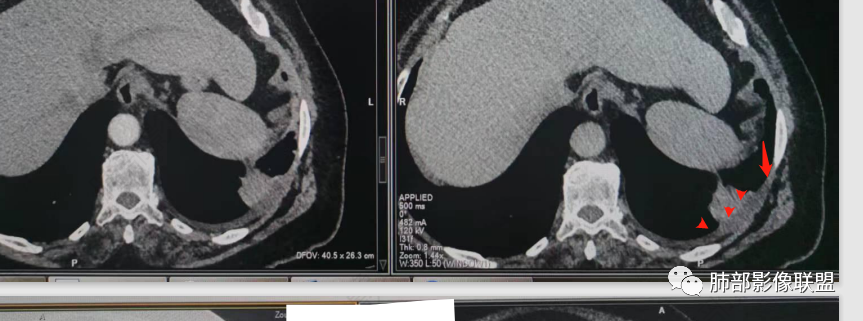

糊墙:肺内病灶不侵犯壁层胸膜或以外,与壁层胸膜相对而言分界清楚。

栽赃:病灶侵入壁层胸膜及胸膜外脂肪间隙、胸壁其他结构等,相对在病灶中央区域,与胸膜分界不清。

南边:看肺内病灶与胸膜分界清,增强后强化不一致,需要综合分析。

这是糊墙。

这就栽赃。都突到外面去了。

看看这个,骨头都侵袭了。

我只是邓较瘦:今天平扫的像栽赃, 增强感觉是增厚的胸膜。

南边:一般这类侵袭,是中央地带毛刷状延伸到胸膜内。

而且旁边这么宽的少,所以觉得很奇怪,不太符合,我是怀疑与照片有关。

你对比一下两侧的密度。肌肉密度不一样。

我只是邓较瘦:南大这个我感觉局部似乎是栽赃呢 箭头那里是啥?

南边:栽赃是这样过去的,中间不会脂肪间隙清晰。

胸壁的组织,除非你怀疑胸壁转移结节。

转移淋巴结。

局部侵犯。有差异。

我只是邓较瘦:这个是侵犯出去不是淋巴结吧?

南边:不是,你看看强化与淋巴结不一致。

我只是邓较瘦:强化与肿瘤差不多。

南边:是。